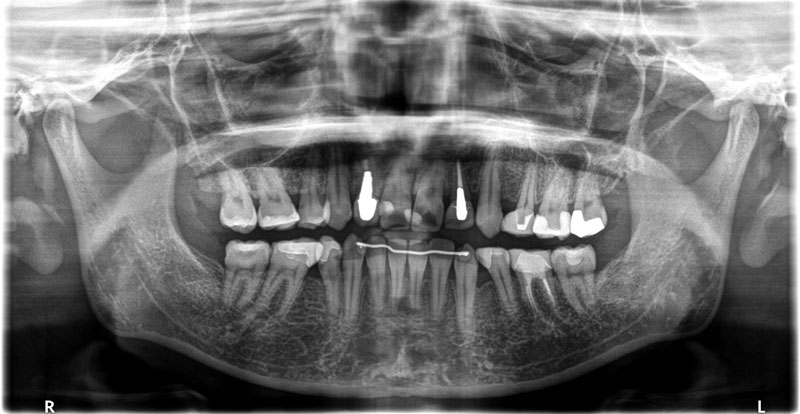

• 初診:2006年、2014年―矯正治療を含めた一口腔単位の治療開始、治療当時、30代女性、非喫煙者

• 治療方針:親知らず3本抜歯、上下小臼歯4本抜歯、矯正用インプラント使用のワイヤー矯正、修復処置、保定(上マウスピース、下ワイヤー)、メンテナンス